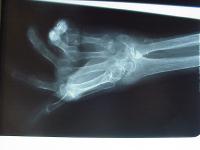

Clinical Example: Rheumatoid arthritis

rheumatoid hand